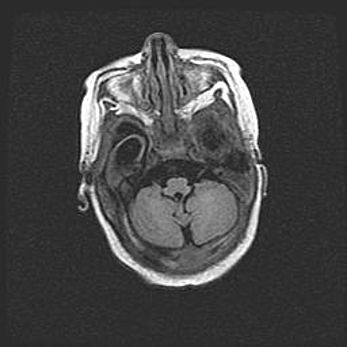

Сообщающаяся гидроцефалия. Кистозная энцефаломаляция головного мозга.

Возраст: 3 месяца 4 дня

Вес: 3100 г

Пол: женский

Окружность головы: 34 см

Срок гестации: 31 неделя

Кистозная энцефаломаляция головного мозга - одна из форм поражения головного мозга в детском возрасте. Характеризуется возникновением множественных и распространённых кист в коре, белом веществе и подкорковых образованиях головного мозга у плодов, новорождённых и детей раннего возраста. Развитие кистозной энцефаломаляции связано с внутриутробной асфиксией и гипотонией, родовой травмой, тромбозом синусов, пороками развития сосудов, инфекциями, сепсисом и другими причинами. Наиболее значимые инфекционные агенты: вирусы простого герпеса, цитомегалии, краснухи, токсоплазмы, энтеробактерии, золотистый стафилококк и другие.